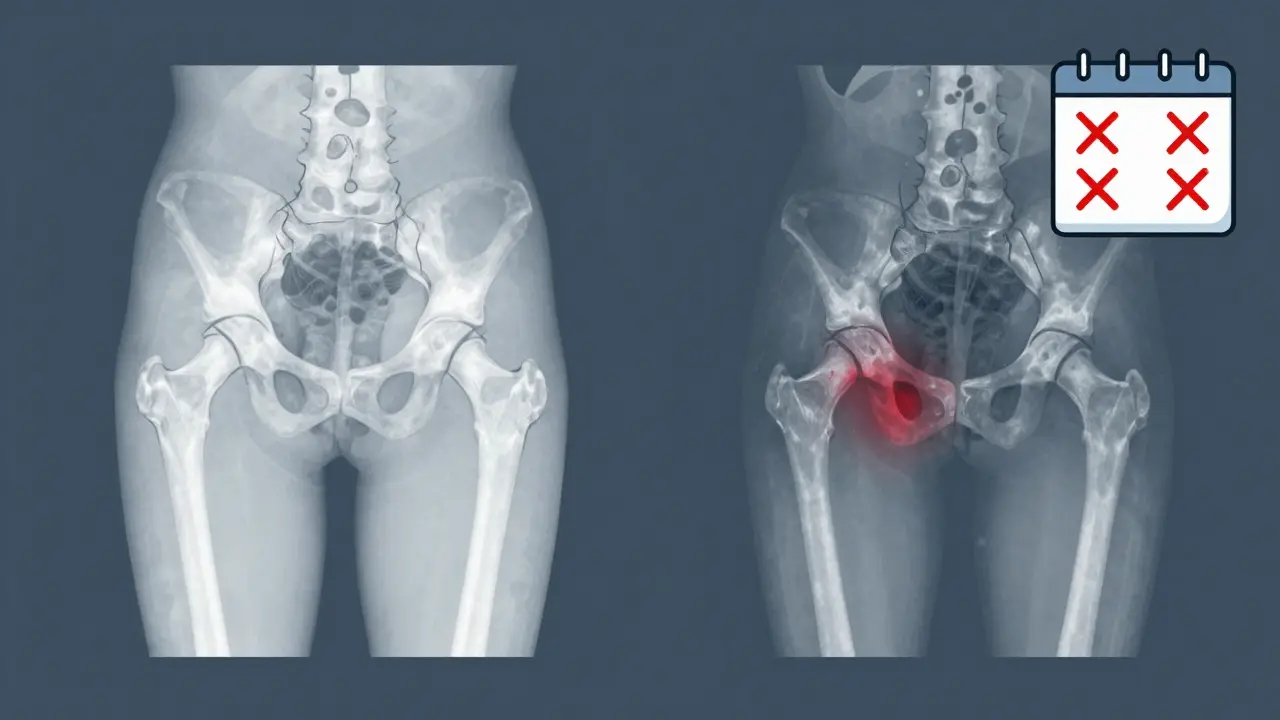

Side-by-side X-rays comparing healthy and damaged hip joints after repeated steroid injections.